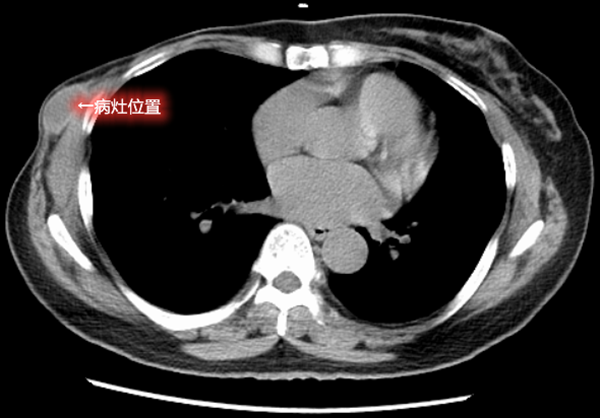

胸部增强ct:左乳腺体及胸壁内见多发结节影,部分相融,增强扫描可见

图片尺寸694x513